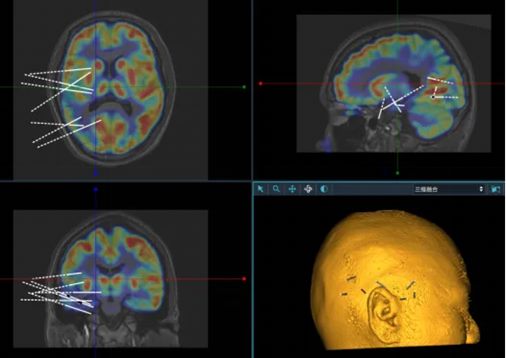

立体定向脑电图技术(stereo-electroencephalography, SEEG)是一种微创的癫痫定位评估方法。该技术最早由法国学者Bancaud和Talairach提出,通过立体定向方式植入脑深部电极,记录癫痫异常放电的起源与传播路径,从时间与空间两个维度进行评估,从而实现对癫痫病灶的精准定位。

通过术后对大脑三维立体网络的定位分析,对于病灶明确、局限的患者,可仅对癫痫灶进行毁损或切除,尽可能保留周围正常的脑组织结构,实现微创治疗。此外,对于位于功能区的癫痫灶,可通过颅内电极电刺激进一步验证手术方案,避免损伤重要神经功能,显著降低手术风险。

术前规划:多模态影像融合,重建大脑三维解剖结构